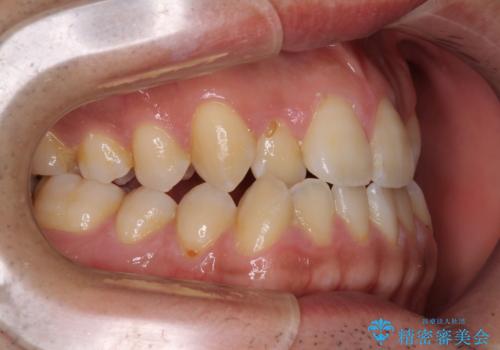

- 前歯のデコボコを気にして来院された患者様です。

歯列としてはワイヤー装置でもインビザラインでも対応可能でしたが、インビザラインが苦手とする上顎側切歯(真ん中から2番目の歯)の舌側転位が顕著でした。

治療の確実性を上げるために、インビザライン開始前に上顎のワイヤー装置にて舌側転位を解消し、その後インビザラインにて矯正治療を行うこととしました。